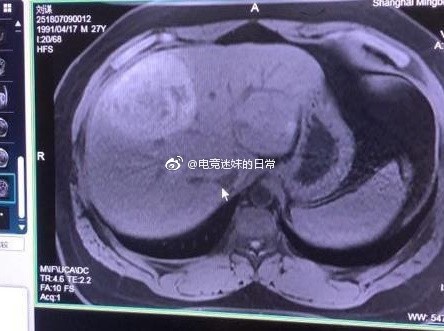

近日,知名游戏博主@电竞迷妹的日常 发微博称,《英雄联盟》主播PDD入院照片和CT扫描图被曝光,被判断可能是原发性肝癌,该消息得到了PDD女朋友沈灵敏的证实:是真的,但是正在做进一步检查,良性概率大一些。 随后不久,PDD发微博表示目前心态良好,良性的概率非常大,也有很多朋友陪在自己身边,会积极面对。 祝愿PDD老师能够早日康复。 |

PDD似患癌称会积极面对:看我神威无坚不摧